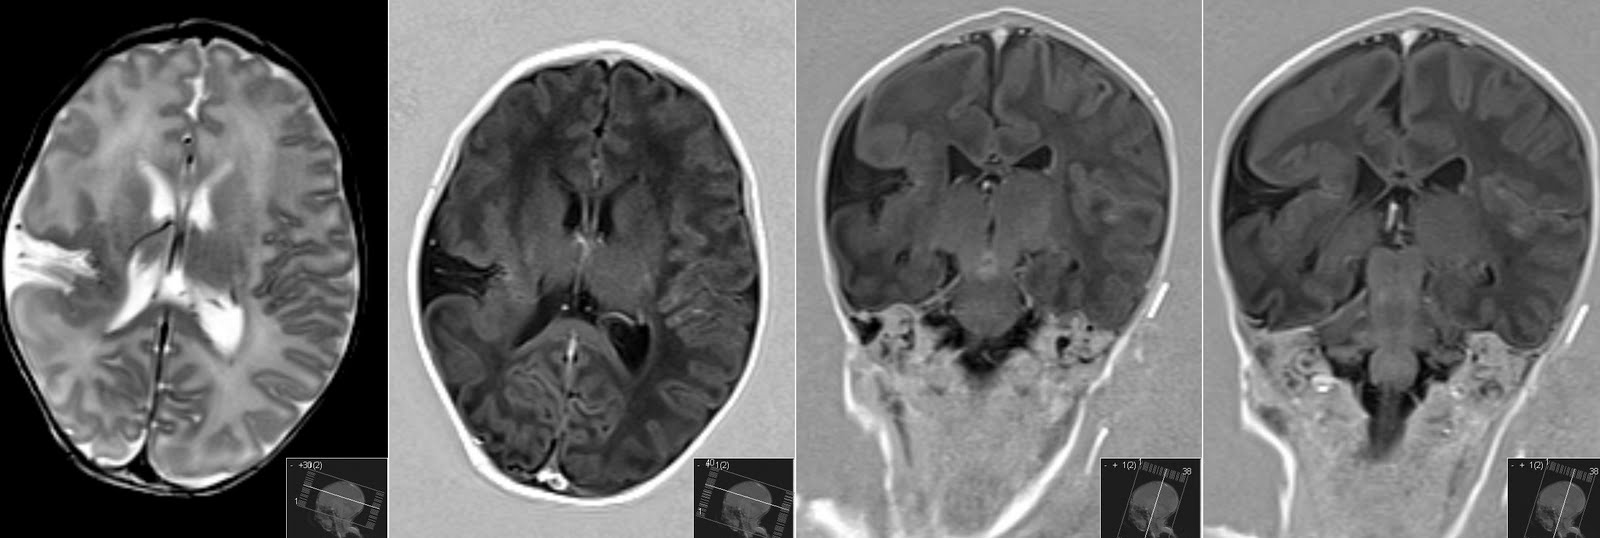

Axial T 1Weighted Brain MRI Showing OpenLip Schizencephaly With Lip Anatomy Mri This article reviews the oral cavity and oropharyngeal anatomy and describe the expected appearance of these structures on routine mri sequences. Understanding the characteristic signal patterns of these lesions in conjunction with clinical presentation is helpful to diagnose pathologies of the oral cavity. We also propose msct and mri acquisition protocols for an accurate study of the oral cavity area.. Lip Anatomy Mri.

Closedlip schizencephaly with a focal cortical dysplasia Image Lip Anatomy Mri Routine postcontrast mr imaging is important for the accurate localization and characterization of the locoregional extension of oral cavity and oropharyngeal cancers. The oral cavity, commonly known as “mouth”, is a part of the digestive system and also helps in. anatomy • the oral cavity consists of the upper and lower lips, gingivobuccal sulcus, buccal mucosa, upper and lower. Lip Anatomy Mri.